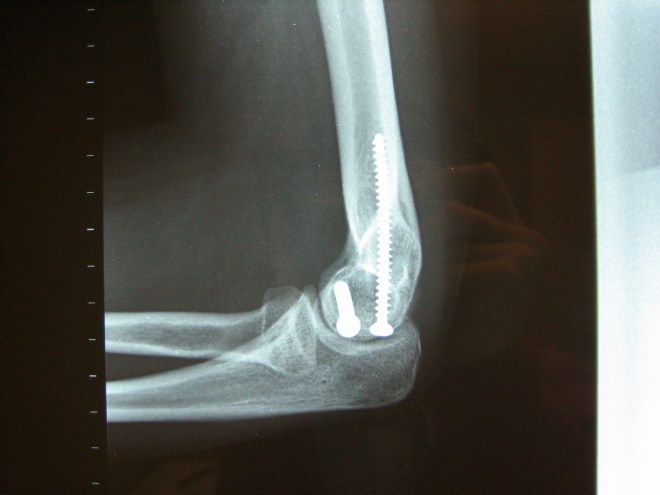

My elbow, which I broke in a freestyle walking competition six years ago. Though the night led to surgery and 6 months of physical therapy, I still think of it fondly.

At a follow-up appointment with my orthopedic surgeon, he took x-rays to examine the 3 mm thick metal plate he told me was attached to my humerus with 4 teeny tiny screws. He clicked on the x-ray screen:

It was just a matter of too many patients to remember, but you can imagine my surprise at seeing two gigantic 3″ screws embedded in my arm. I’ve since grown quite fond of my bionic elbow, though, it never sets off airport metal detectors like I hope it might.